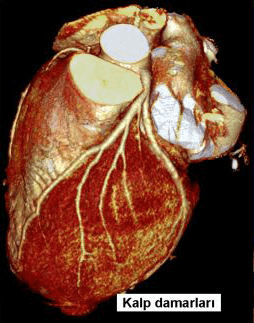

BT anjiografide de tıpkı MR anjiografide olduğu gibi vücuttaki tüm damarlar incelenebilir. Özellikle koroner kalp damarlarının incelenmesinde günümüzde klasik kalp anjiosuna alternatif bir yöntem haline gelmiştir. Ayrıca karın, beyin ve boyun damarlarının görüntülenmesinde de birçok durumda klasik periferik anjiografinin yerini almıştır. Görüntüler MR’ a göre daha net olduğundan ve hareket artefaktlarından daha az etkilendiğinden, BT anjiografi görüntüleri MR anjiografiye göre daha kaliteli ve güvenilirdir. Ancak BT anjiografide hasta radyasyon alır ve mutlaka damardan ilaç (kontrast madde) vermek gerekir. Bu ilaç özellikle böbrek yetmezliği olan hastalarda dikkatli kullanılmalıdır. Ayrıca her incelemede sınırlı bir alan taranabilir. Bu özellikleriyle BT anjiografi genellikle klasik anjiografi yapmadan önce uygulanan ve bazı hastalarda klasik anjiografinin yerini tutabilen bir yöntemdir. En önemli üstünlüğü sadece damarın içini değil damar duvarını da gösterebilmesi ve duvar içinde yer alan kan, pıhtı ya da henüz damarda belirgin tıkanma yaratmayan ateroskleroz gibi patolojileri de gösterebilmesidir.